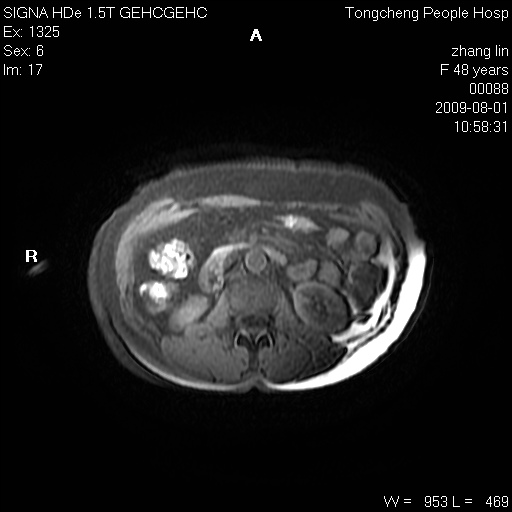

女,48岁。健康体检,彩超发现右肾占位性病变。平素健康。

临床诊断:右肾占位性病变,性质待定(囊肿?肿瘤?)。

上中腹部mr平扫+增强扫描,图像如下:

右肾上极见一类圆形病灶,t1wi呈等信号t2wi呈等高混杂信号,三期增强无强化,边界清---考虑囊肿出血。

同反相位均表现为等信号,病变无强化,考虑含蛋白的囊肿可能,弥散加权相或许有些帮助,

慢性胆囊炎